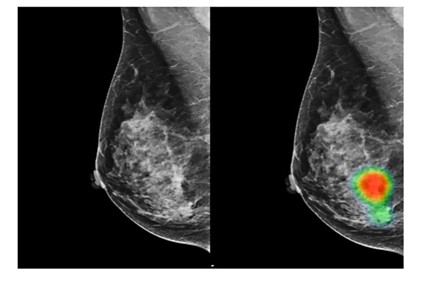

- Finding Breast Cancer: A South Korean study found that an AI-based tool achieved 90% sensitivity in detecting breast cancer with mass, outperforming radiologists who achieved 78%. The same system also demonstrated superior capabilities in early breast cancer detection with 91% accuracy compared to radiologists at 74%.

The system is designed to learn when to rely on the AI’s prediction and when to “defer to a clinician.” In one test scenario using a large mammography dataset, this collaborative approach reduced the number of false positives by 25% compared to standard clinical workflows, all without missing any true positive cases. This ensures that the final decision is always made using the best of both worlds.